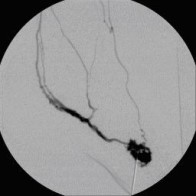

Postoperative abdominelle Blutungen bei chronischer Pankreatitis (Pfeile: Art. hepatica und Art. gastroduodenalis).

(Bild 1 von 5)

Postoperative abdominelle Blutungen bei chronischer Pankreatitis vor Embolisation der Art. gastroduodenalis mittels Metallspiralen (Coils)

(Bild 2 von 5)